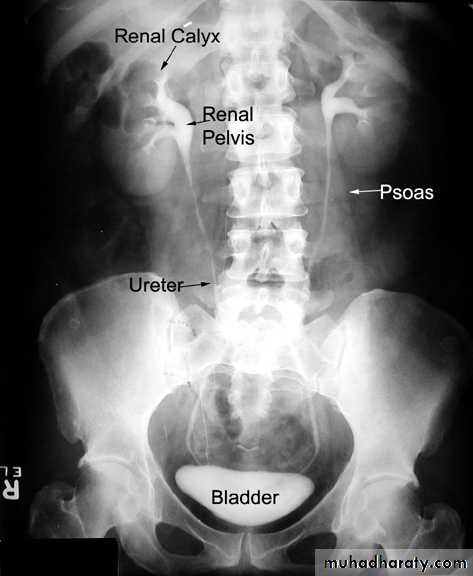

Normal IVU

nephrogram

pyelogram